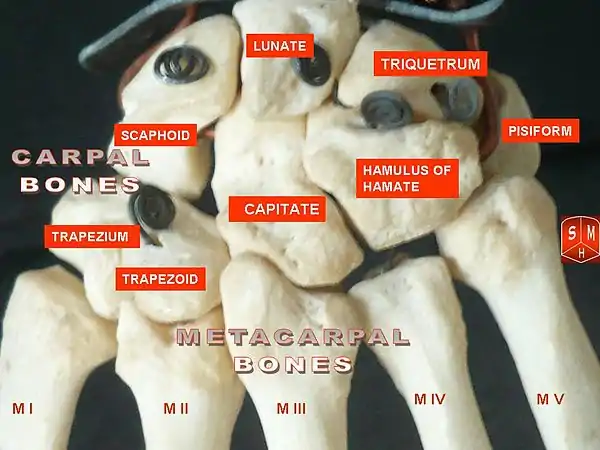

The bones in the hand The carpal and metacarpal bones in the hand

The carpal and metacarpal bones in the hand X-ray of the bones in the hand